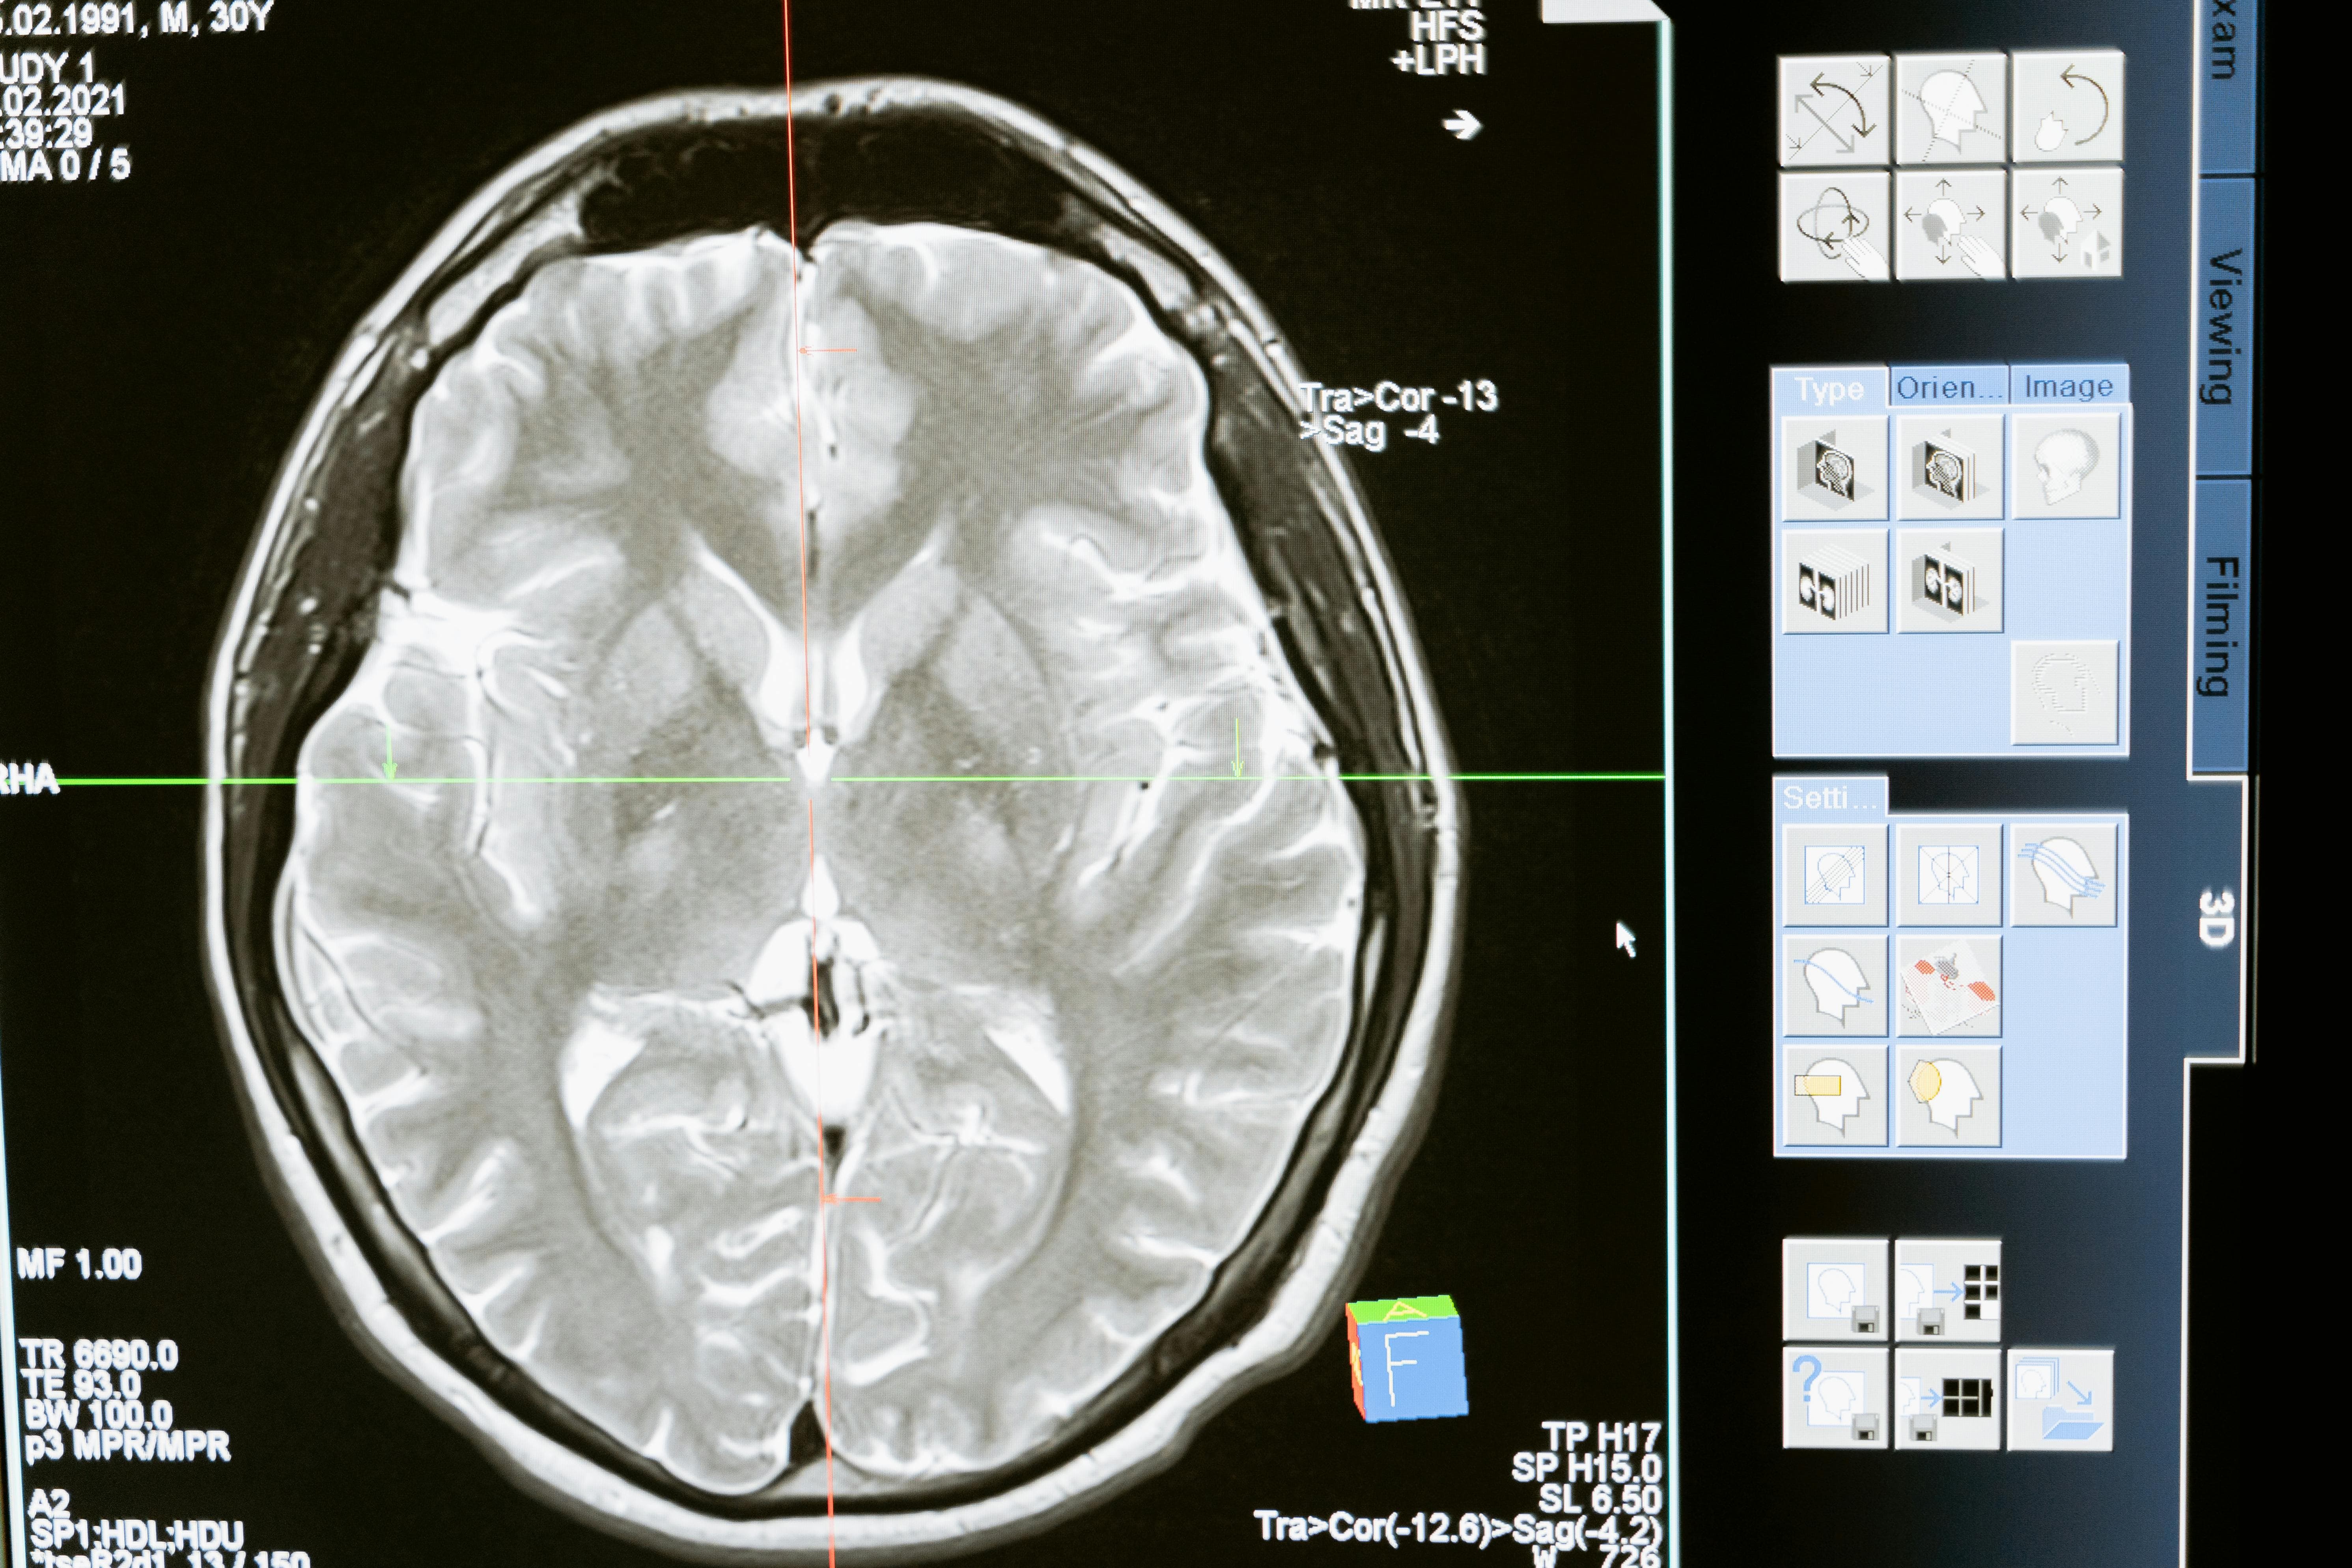

1️⃣ MRI 검사, 언제 실손 적용이 될까

MRI는 의사의 판단에 따라 치료 목적으로 필요성이 인정될 경우 실손보험 적용 대상이 되는 경우가 많습니다.

하지만 다음과 같은 상황에서는 본인 부담금이 크게 늘어날 수 있습니다.

- 단순 확인 목적의 검사

- 증상이 명확하지 않은 상태에서의 촬영

- 보험 약관상 보장 제외 항목

즉 찍었느냐 보다 왜 찍었느냐 가 중요합니다.